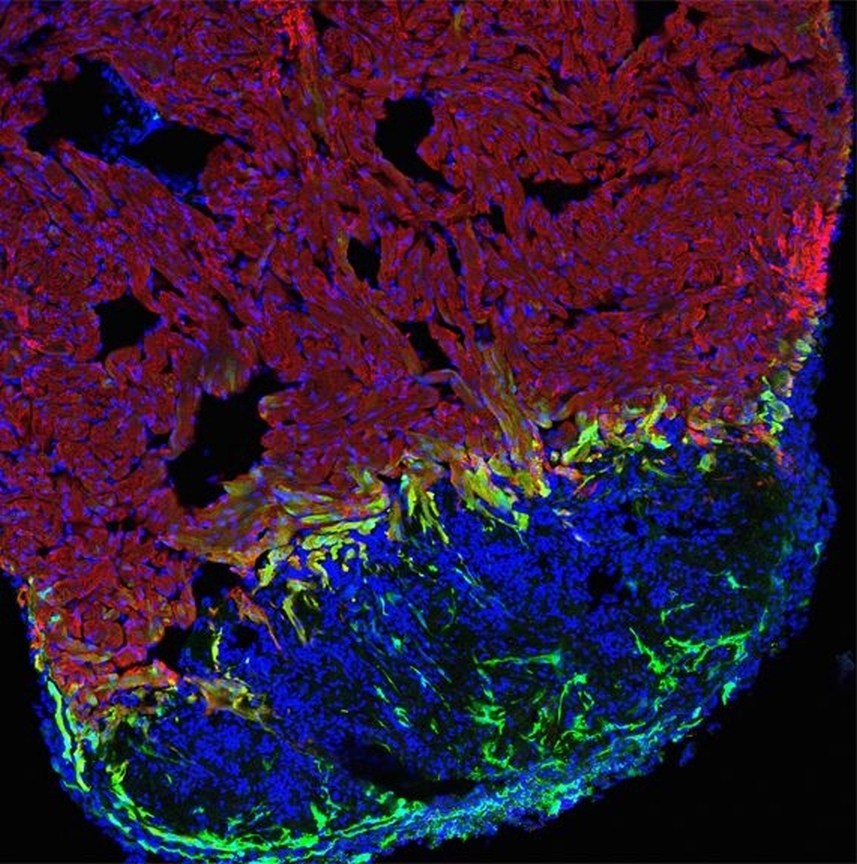

* gesundes Muskelgewebe rot, Wunde blau und aktivierte Herzmuskelzellen grün angefärbt

„Das verletzte Gewebe regeneriert sich durch die vermehrte Zellteilung von Herzmuskelzellen an der Wundgrenze“, erklärt Professor Gilbert Weidinger vom Institut für Biochemie und molekulare Biologie der Universität Ulm. Wie das internationale Forscherteam – an dem neben dem Weidinger-Labor auch Wissenschaftler des Uni-Klinikums Utrecht beteiligt sind – zeigen konnte, wird die Zellvermehrung über ein besonderes Protein gesteuert: das sogenannte bone morphogenetic protein (BMP). BMP ist ein wichtiges Signalprotein der Zell-Zell-Kommunikation. Die Forscher konnten nachweisen, dass es insbesondere im Wundbereich reaktiviert wird, wo gesundes und verletztes Gewebe aufeinander stoßen.

So wiesen die Wissenschaftler nach, dass das BMP-Signal von Herzmuskelzellen aktiviert wird, die aus dem Grenzbereich zwischen gesundem und verletztem Herzmuskelgewebe kommen. Mit Hilfe von transgenen Zebrafischlinien, bei denen der BMP-Signal-Weg einerseits blockiert und andererseits verstärkt wurde, konnten die Forscher den Regenerationsprozess gezielt beeinflussen. Bei der genetisch veränderten Variante mit blockiertem BMP-Signal-Weg waren Zellvermehrung und damit die Regenerationsfähigkeit deutlich reduziert. Bei der Variante mit überaktivem BMP konnte die Regeneration dagegen sogar forciert werden.